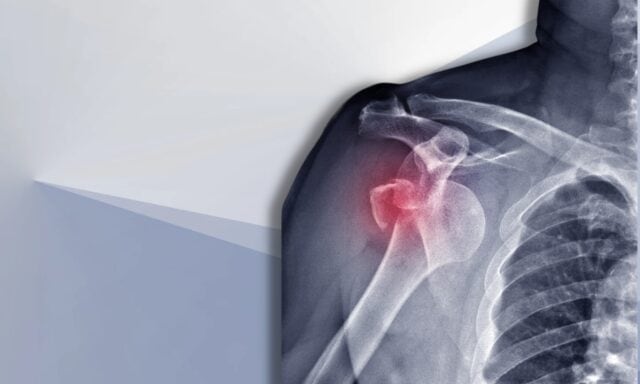

Instabiele schouder

In deze aflevering praten we over alles wat met schouderinstabiliteit te maken heeft. U leert meer over de Stanmore classificatie en structurele schade na dislocaties. Wij bespreken de typische patiënt met schouderinstabiliteit en hoe een onderzoeksproces eruit ziet. We zullen ingaan op spieractiveringspatronen, chirurgie en hoe fysiotherapeutische behandeling van een patiënt met schouderinstabiliteit er mogelijk uit zou kunnen zien. Luister dus zeker naar de hele aflevering!